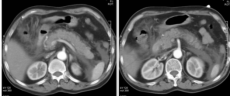

1腺炎CT表现:多数有胰腺弥漫性增大,少数轻者表现正常;密度正常或略减低,均匀或不均匀;胰腺轮廓清楚或模糊,渗出明显者可有胰周积液;肾前筋膜及肾周筋膜增厚;增强扫描胰腺均匀强化。

肾旁前间隙、肾后间隙积液

腺炎MRI表现:胰腺局限/弥漫肿大,呈T1低信号、T2高信号;胰腺轮廓清楚或模糊,渗出明显者可有胰周 或胰外积液,呈T1低信号、T2高信号;合并出血,T1T2皆呈高信号;增强扫描:水肿型,胰腺均匀强化 ;坏死型,胰腺不均匀强化,坏死区无明显强化。

慢性胰腺炎CT表现:胰腺体积大小可正常,也可增大或缩小,改变可呈局限性或弥漫性。弥漫性萎缩也见于糖尿病病人及老年人;胰管扩张:多显示不同程度扩张,可呈管状或串珠状;胰管结石和胰实质钙化。